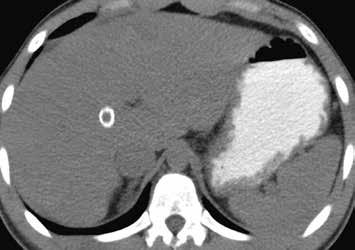

Nativně na CT je nezřetelně naznačeno několik hypodenzních ložisek (17). Všechna se vcelku homogenně sytí v arteriální fázi (18). V portovenózní fázi je sycení jater celkově nehomogenní, ložiska jsou však nadále lehce hyperdenzní oproti okolnímu parenchymu jater (19).